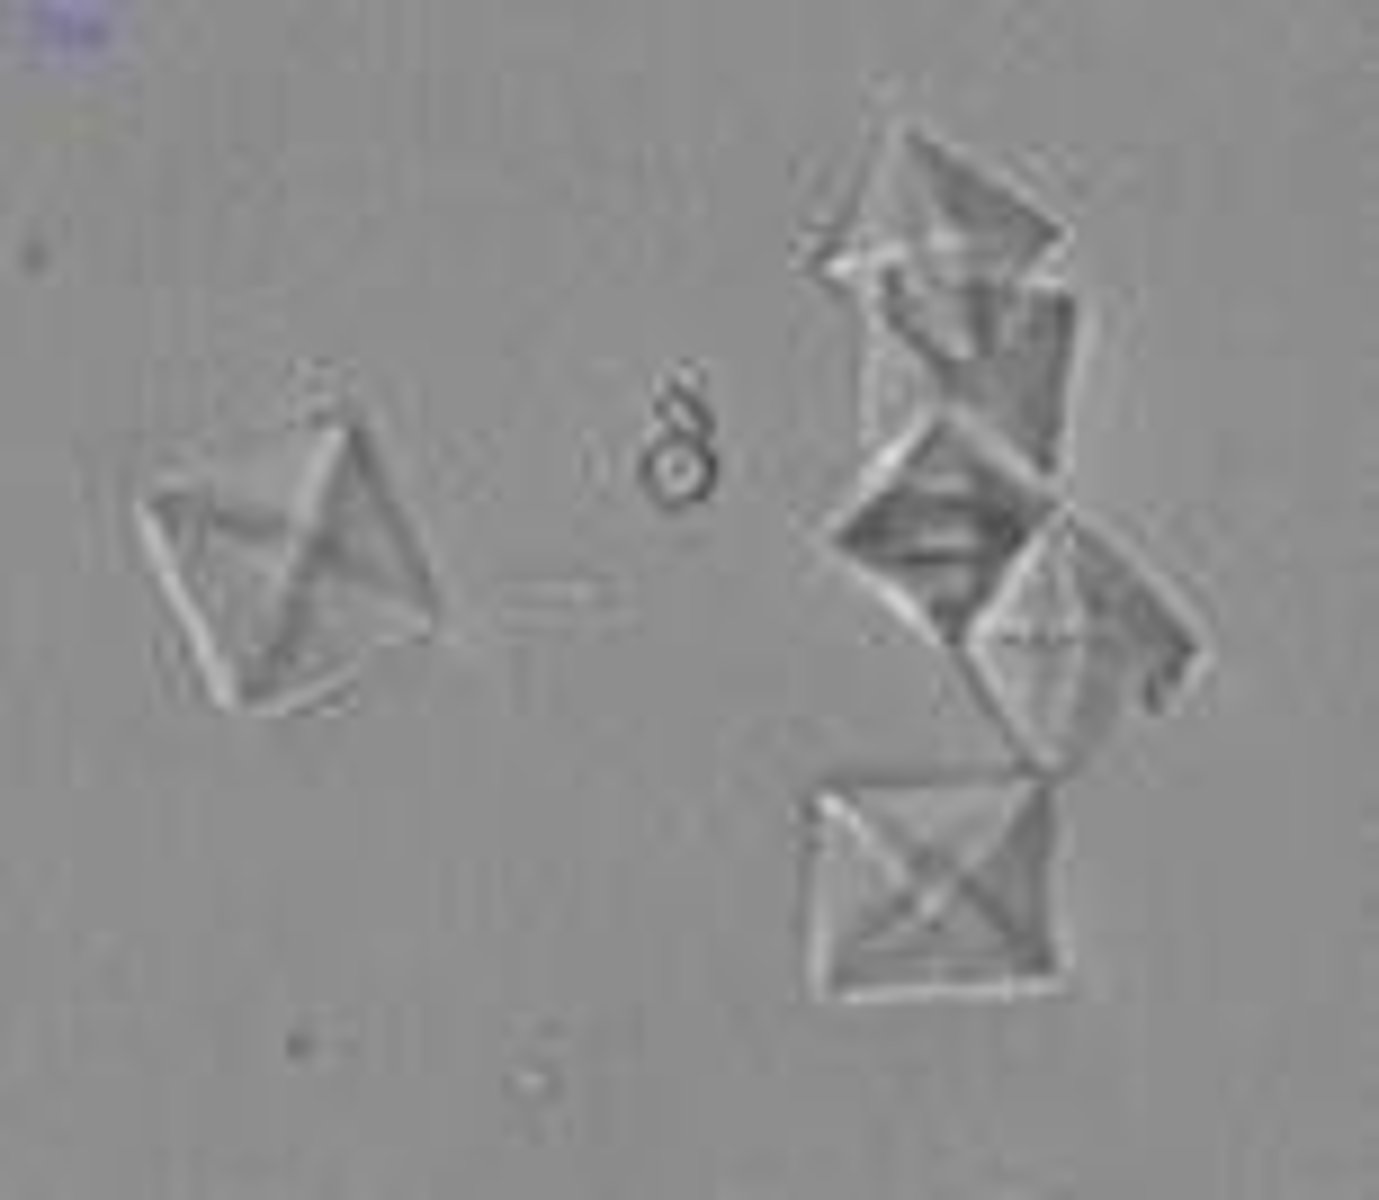

calcium oxalate crystals

urine

colorless, square with x inside

calcium oxalate monohydrate

urine

elongated, 6 sided, crystal with ends

antifreeze toxicity